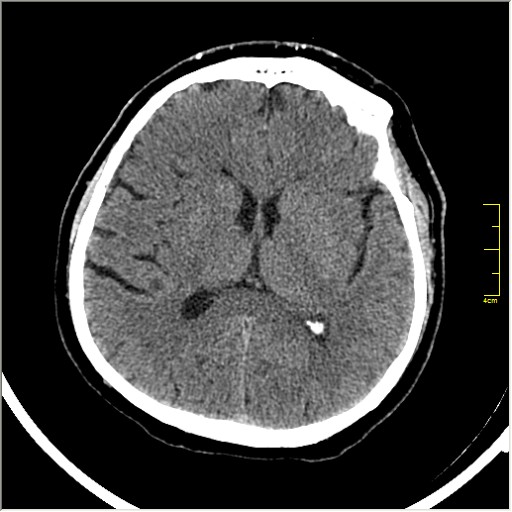

Этот признак называется [Dense MCA sign]; за счёт наличия тромбоза в её просвете. Этот признак является одним из ранних указующих КТ признаков при ишемическом инфаркте головного мозга. Более подробно об этом вы можете прочитать здесь: http://www.radiologyassistant.nl/en/483910a4b6f14.

Ну и для полноты картины, привожу контрольные КТ сканы выполненные через 24 часа: